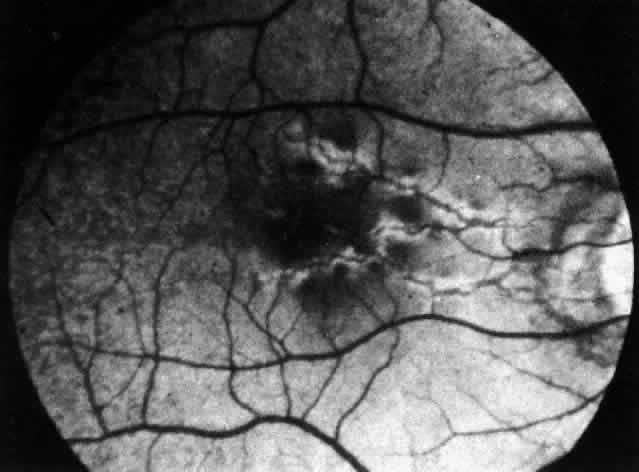

Pemphigus can be differentiated from bullous pemphigoid and from cicatricial pemphigoid on histologic and immunologic bases. Whereas the bullae in pemphigus are intraepidermal, those occurring in bullous pemphigoid and in cicatricial pemphigoid are subepidermal, between epidermis and dermis, or between mucosa and submucosa. Acantholysis is not present in the latter two conditions.5 In bullous pemphigoid and in cicatricial pemphigoid there are tissue-fixed immunoglobulins in the subepidermal basement membrane zone (Fig. 2).11 This is in contrast to the interepidermal fixation of antibodies (Fig. 3) seen in pemphigus (Table 1).